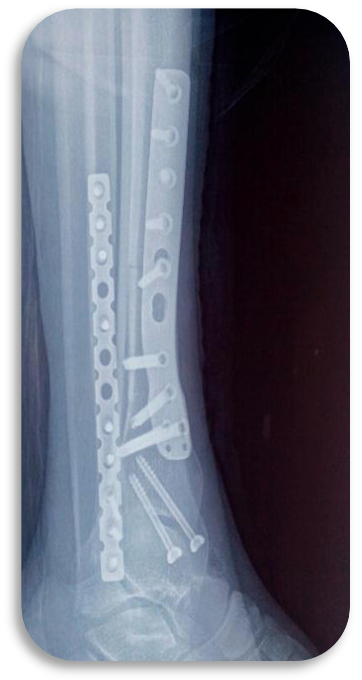

胫骨骨折微创钢板Case1

胫骨骨折微创钢板Case2

胫骨骨折微创钢板Case3

胫骨骨折微创钢板Case4

胫骨骨折切开钢板Case1

胫骨骨折切开钢板Case2

胫骨骨折切开钢板Case3

胫骨骨折微创髓内钉Case4